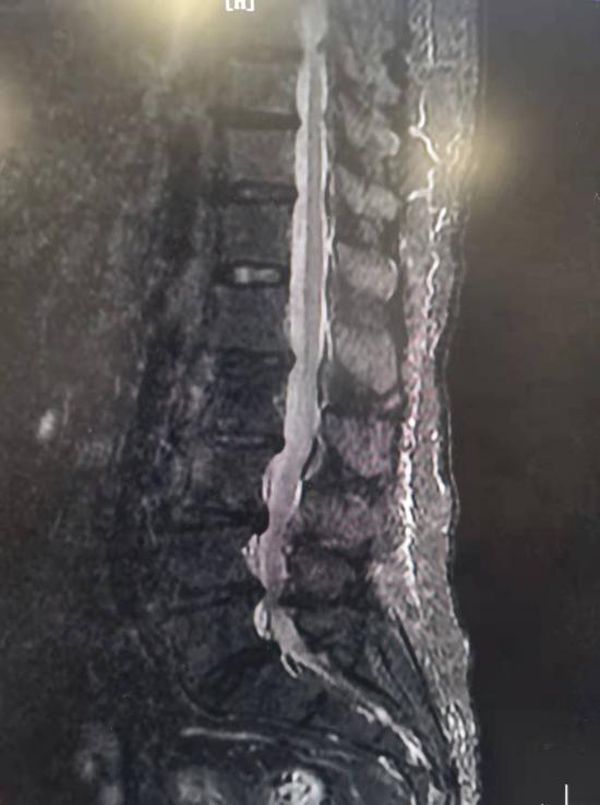

73岁的王奶奶患有严重的椎管狭窄,伴椎间盘突出,这一病就是好几年,患病期间,王奶奶走几百米腿痛腰痛,就得坐下来休息,夜间更是下肢抽痛、难以入睡,随着病情进一步加重,王奶奶来到陕西省核工业二一五医院脊柱脊髓外科,经检查提示为骨质增生、椎管狭窄、椎间盘突出......

腰1--骶1椎间盘膨出,腰5-骶1椎间盘突出,腰3--骶1椎管狭窄。腰3椎体不稳,腰椎骨质增生。

韧带肥厚,椎管狭窄,神经明显卡压。